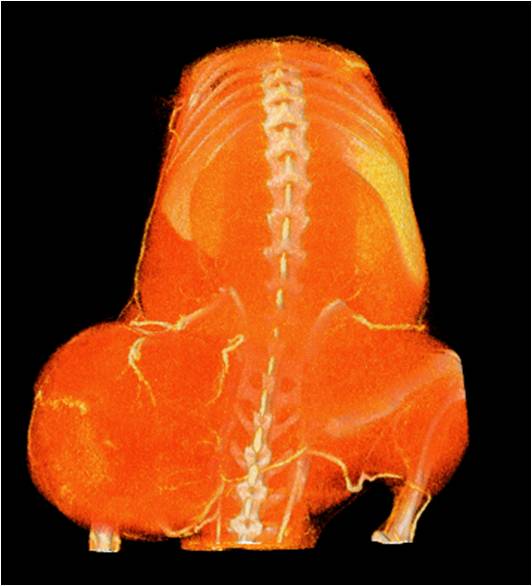

腫瘤血管生成

肺轉(zhuǎn)移

小鼠模式,22.5μm像素

正常

8天 14天

無(wú)造影劑注入 造影劑注入